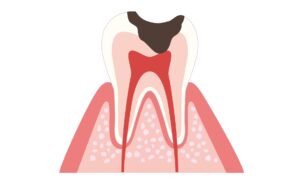

放置厳禁!虫歯の進行度をわかりやすく解説

虫歯には進行ステージがあり、治療内容も異なってきます。

④ C3(神経に進行):強い痛み

C3は神経まで虫歯が到達し、歯がズキズキした痛みを感じる事が多いです。

夜寝られないぐらい痛むことがあるので、歯の異変を大きく感じるタイミングでしょう。

C3まで進行した虫歯は根の治療が必要になります。

根の治療は歯の神経を取り、しっかり感染した部分を取り除いたのち、被せ物を立てていく処置となります。